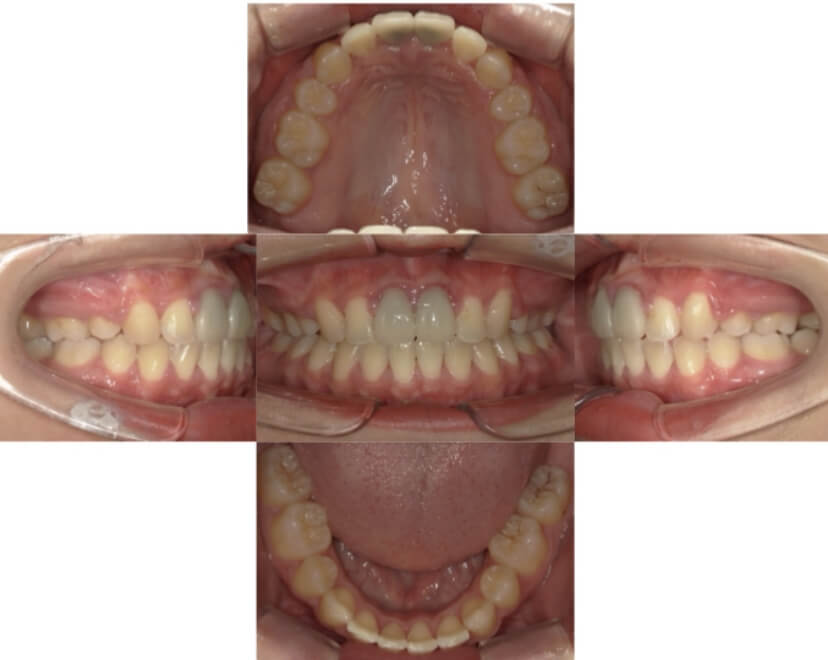

BEFORE

AFTER

上下顎叢生、上顎前突(出っ歯、上下の前歯のガタガタ)のケースです。

装置はラビアル(上下表側)で、上顎の小臼歯を2本抜歯を行っています。抜歯したスペースを使って、上の前歯の後方移動と叢生(ガタガタ)と出っ歯の改善を行っています。下は歯と歯の間にIPR(隣接面削合)を行い、スペースを確保し、叢生の改善を行っています。

主訴 前歯のガタガタと出っ歯が気になる。

年齢・性別 47歳 女性

お住まいの地域 神奈川県川崎市

治療方針 抜歯スペースおよびIPRを利用して上前歯の叢生(ガタガタ)の改善

抜歯部位 上顎左右第一小臼歯

使用装置 ラビアル(上下表側)、顎間ゴム

治療期間 2年0か月

治療回数 15回

リテーナー クリアリテーナー